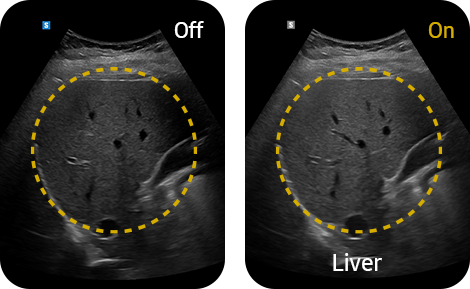

Clean up blurry areas

in the image

HQ-Vision™ ¹ provides clearer images by mitigating the characteristics of ultrasound images that are slightly blurred than the actual vision.